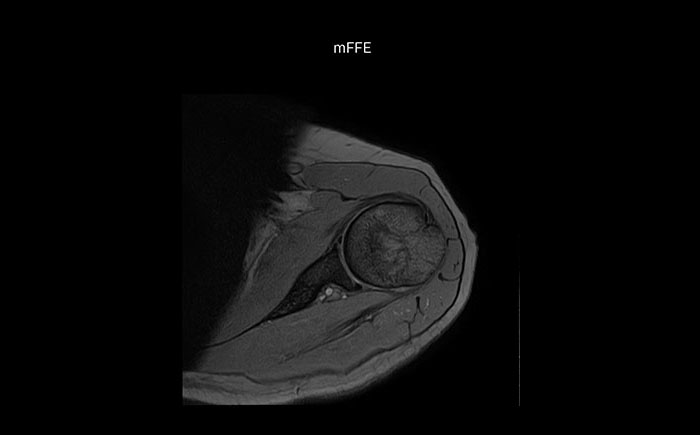

The Prodiva shoulder coil is very flexible and has large coverage, which makes good positioning easier, and that contributes to the superb image quality and high SNR that we get in our shoulder exams.

Scan time 2:55 min, FOV 160 mm, acq voxels 0.55 x 0.83 x 3.0 mm.

Scan time 4:19 min, FOV 160 mm, acq voxels 0.55 x 0.80 x 3.0 mm.

Scan time 2:50 min, FOV 160 mm, acq voxels 0.70 x 0.99 x 3.0 mm.